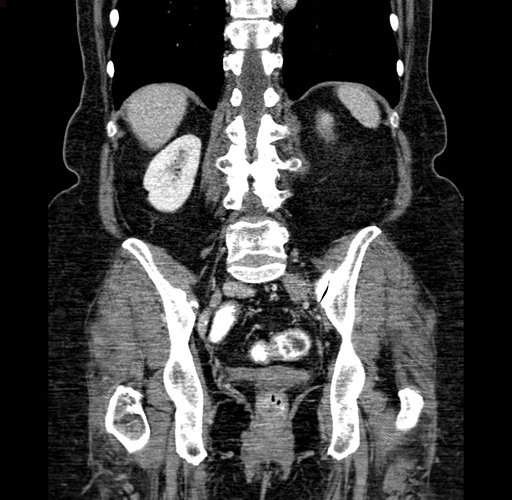

Pre-Chemo: Coronal Venous